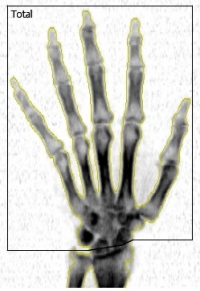

Kości obu rąk |

|

Wysoce specjalistyczna procedura, przeznaczona dla pacjentów w diagnostyce bólów i obrzęków drobnych stawów rąk w przebiegu różnych procesów zapalnych. Umożliwia monitorowanie zmian gęstości mineralnej kości rąk (ang. bone mineral density - BMD).